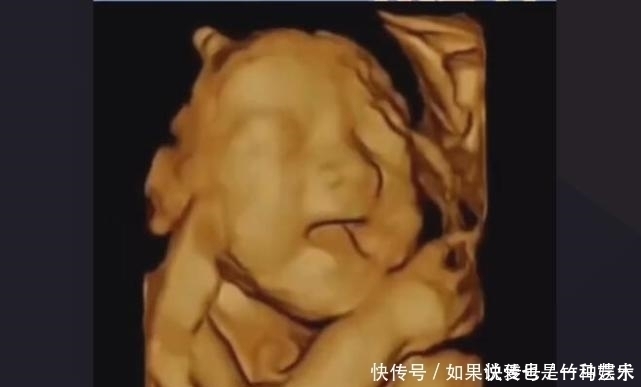

文章插图